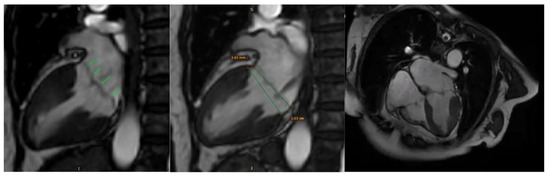

Additionally, contrast-enhanced cardiac magnetic resonance imaging (MRI) confirmed the previously described findings, including bileaflet mitral valve prolapse with leaflet redundancy, severe mitral regurgitation, and mitral annular disjunction. The left ventricle was of normal size and function, and there was no late gadolinium enhancement (LGE), indicating the absence of myocardial fibrosis (Figure 8).

Figure 8.

Mitral valve prolapse and mitral annulus disjunction (MAD) on cardiac magnetic resonance (CMR). Green arrows indicate myxomatous valve changes and mitral valve prolapse. Green lines illustrate mitral annular disjunction (MAD), represented as the distance between the two lines: the first drawn at the level of the mitral annulus and the second at the level of the ventricular myocardium.